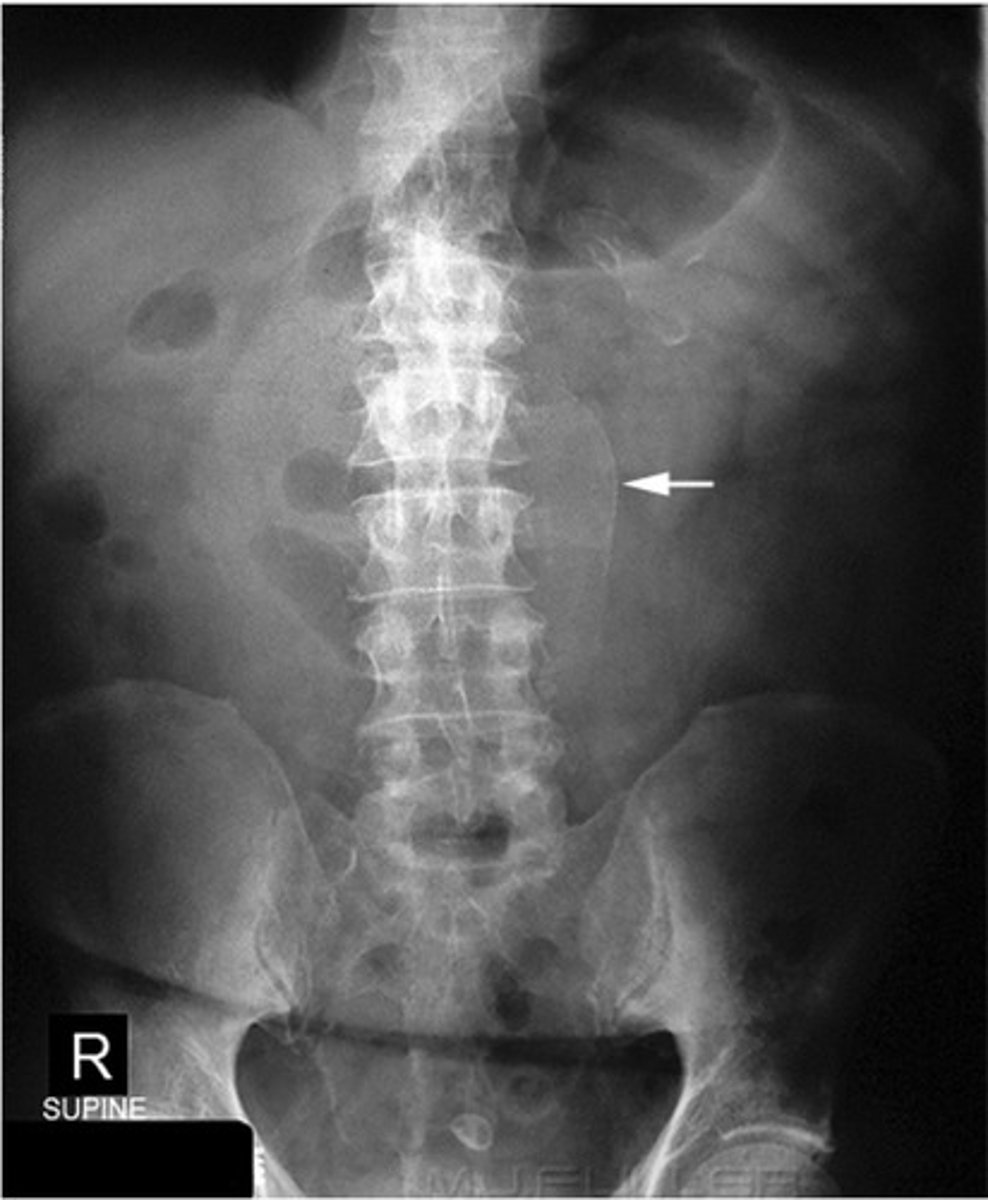

Abdominal aortic aneurysm calcification

Abdominal aortic aneurysm calcification (pic 2)

Abdominal aortic aneurysm calcification (pic 3)